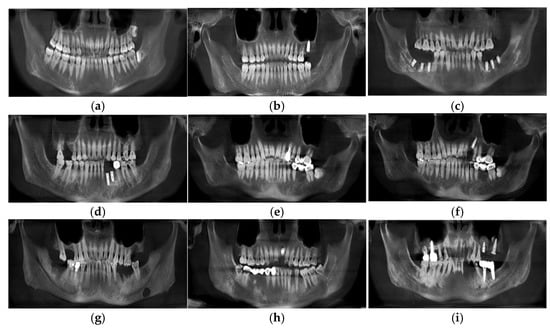

3.3. Different Types of Panoramic Image Effects